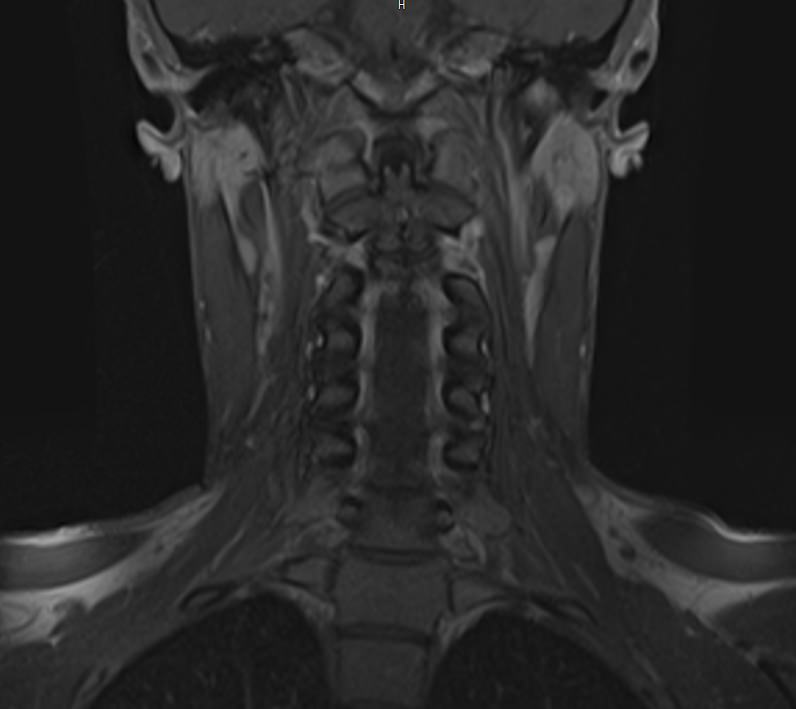

Магнитно-резонансная томография является современным, высокоинформативным и доступным методом обследования позвоночника. МРТ позволяет оценить состояние костных структур позвонков, спинного мозга, нервных корешков и окружающих мягких тканей. С помощью МРТ можно диагностировать грыжевые выпячивания межпозвонковых дисков, степень их воздействия на нервные корешки и спинной мозг.

Но несмотря на высокую диагностическую ценность магнитно-резонансной томографии, в некоторых случаях для улучшения визуализации патологических очагов дополнительно применяется контрастное усиление. В частности, при подозрении на опухоли позвоночника или спинномозгового канала, для оценки активности очагов демиелинизации спинного мозга, требуется внутривенное введение контраста.

В клинике «Доступная медицина» выполняется МРТ различных отделов позвоночника. В зависимости от уровня поражения можно провести МР томографию шейного отдела, грудного отдела, пояснично-крестцового отдела позвоночника и копчика.